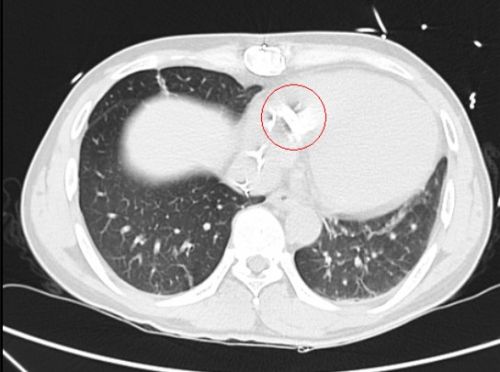

术前ct片上可以看到患者体内的人工瓣膜。